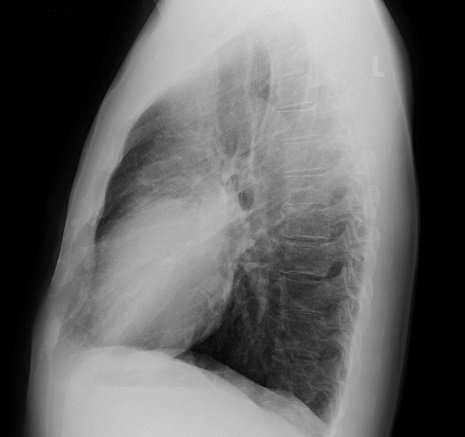

Abb.2: Röntgenaufnahme Lungenentzündung – Aufnahme von der Seite. Zum Vergößern auf das Bild klicken.